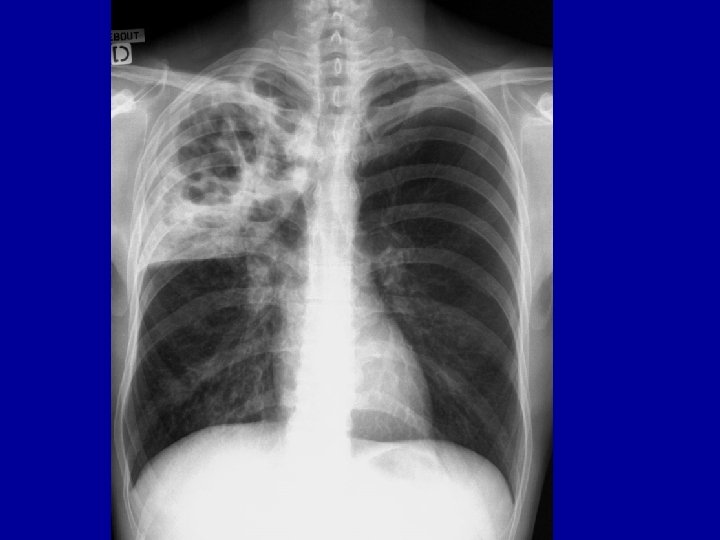

Les complications graves = SIDA • Tuberculose – Première complication du SIDA dans le Monde – Difficultés de traitement – Nécessité d’un traitement long (6 mois) et lourd – Interactions antirétroviraux – si mal pris = RISQUE D’ACQUISITION DE RESISTANCES » Évolution vers des formes multirésistantes TRANSMISSIBLES – Formes cliniques • Pulmonaires (contagiosité +++) • Ganglionnaires • Disséminées – Diagnostic • Clinique • Mise en évidence des bactéries (pas toujours)

Les complications graves : SIDA • La pneumocystose – Infection pulmonaire – Clinique • En général apparition progressive • Dyspnée, toux • Image pulmonaire – Diagnostic : lavage broncho-alvéolaire – Peut être grave • mortalité 100% en l’absence de soins – Thérapeutique disponible • Triméthoprime-Sulfaméthoxazole – Fortes doses – Risques d’intolérance – Prophylaxie secondaire nécessaire (TMP-SMX)